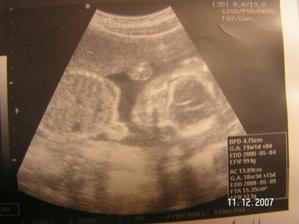

Tak jsme zpět z poradny.Jestli to bude kluk nebo holčička nevíme,protože miminko překřížilo nožky a nechtělo se ukázat.Za to na mamku krásně mávalo,tak to pan doktor zvěčnil-fotka je v albíčku.Měříme už 11cm!!!Zítra - 14.11. jdeme na tripple testy a taky na kontrolu,mamce totiž začalo nějak tvrdnout bříško,tak to pan doktor raději zkontroluje.Snad je všechno v pořádku.///Tak dneska 14.10.-na kontrole všechno v pořádku,jen placenta je trochu moc dole,ale to by se mělo do dvou měsíců upravit,mimi je o pět dní menší,ale krásné.(viz. foto).Dostali jsme magnézko na to tvrdnutí.Nabrali mi krev na tripple testy,tak se bojím,aby to bylo v pořádku.///Tak na testech jsme měli nakonec něco mírně zvýšené,ale celkem ještě v normě,tak doufám,že 12.12. na velkém genetickém UZ bude všechno v pořádku.A třeba se už konečně dozvíme,co to vlastně čekáme.///Tak jsme byli na genet.UZ-všechno je naprosto v pořádku!!!Mimi váží 360g a měří 25cm.Jsme 20+5tt.A víme,co to bude!Holčička!!!///Narazila jsem na úžasný kočárek,byla jsem z něho tak unešená,že jsme ho malé Fazolce museli pořídit.///7.1.-KO v poradně.Princezna má už 633g!!Všechno je v pořádku.Příští týden na cukrovkový test-FUJ!Můj váhový přírustek zatím 4,5kg-24+6tt.///Včera-4.2. kontrola v poradně.Všechno v pořádku.Vážíme 1255g a měříme přes 30cm.Můj váhový přírůstek - 29.tt.-asi 5,5 kg.///3.3.2008-velký UTZ,všechno v pořádku,akorát mám špatný krevní obraz,takže budeme zobat železo.Můj váhový přírůstek 7kg-33.tt.////